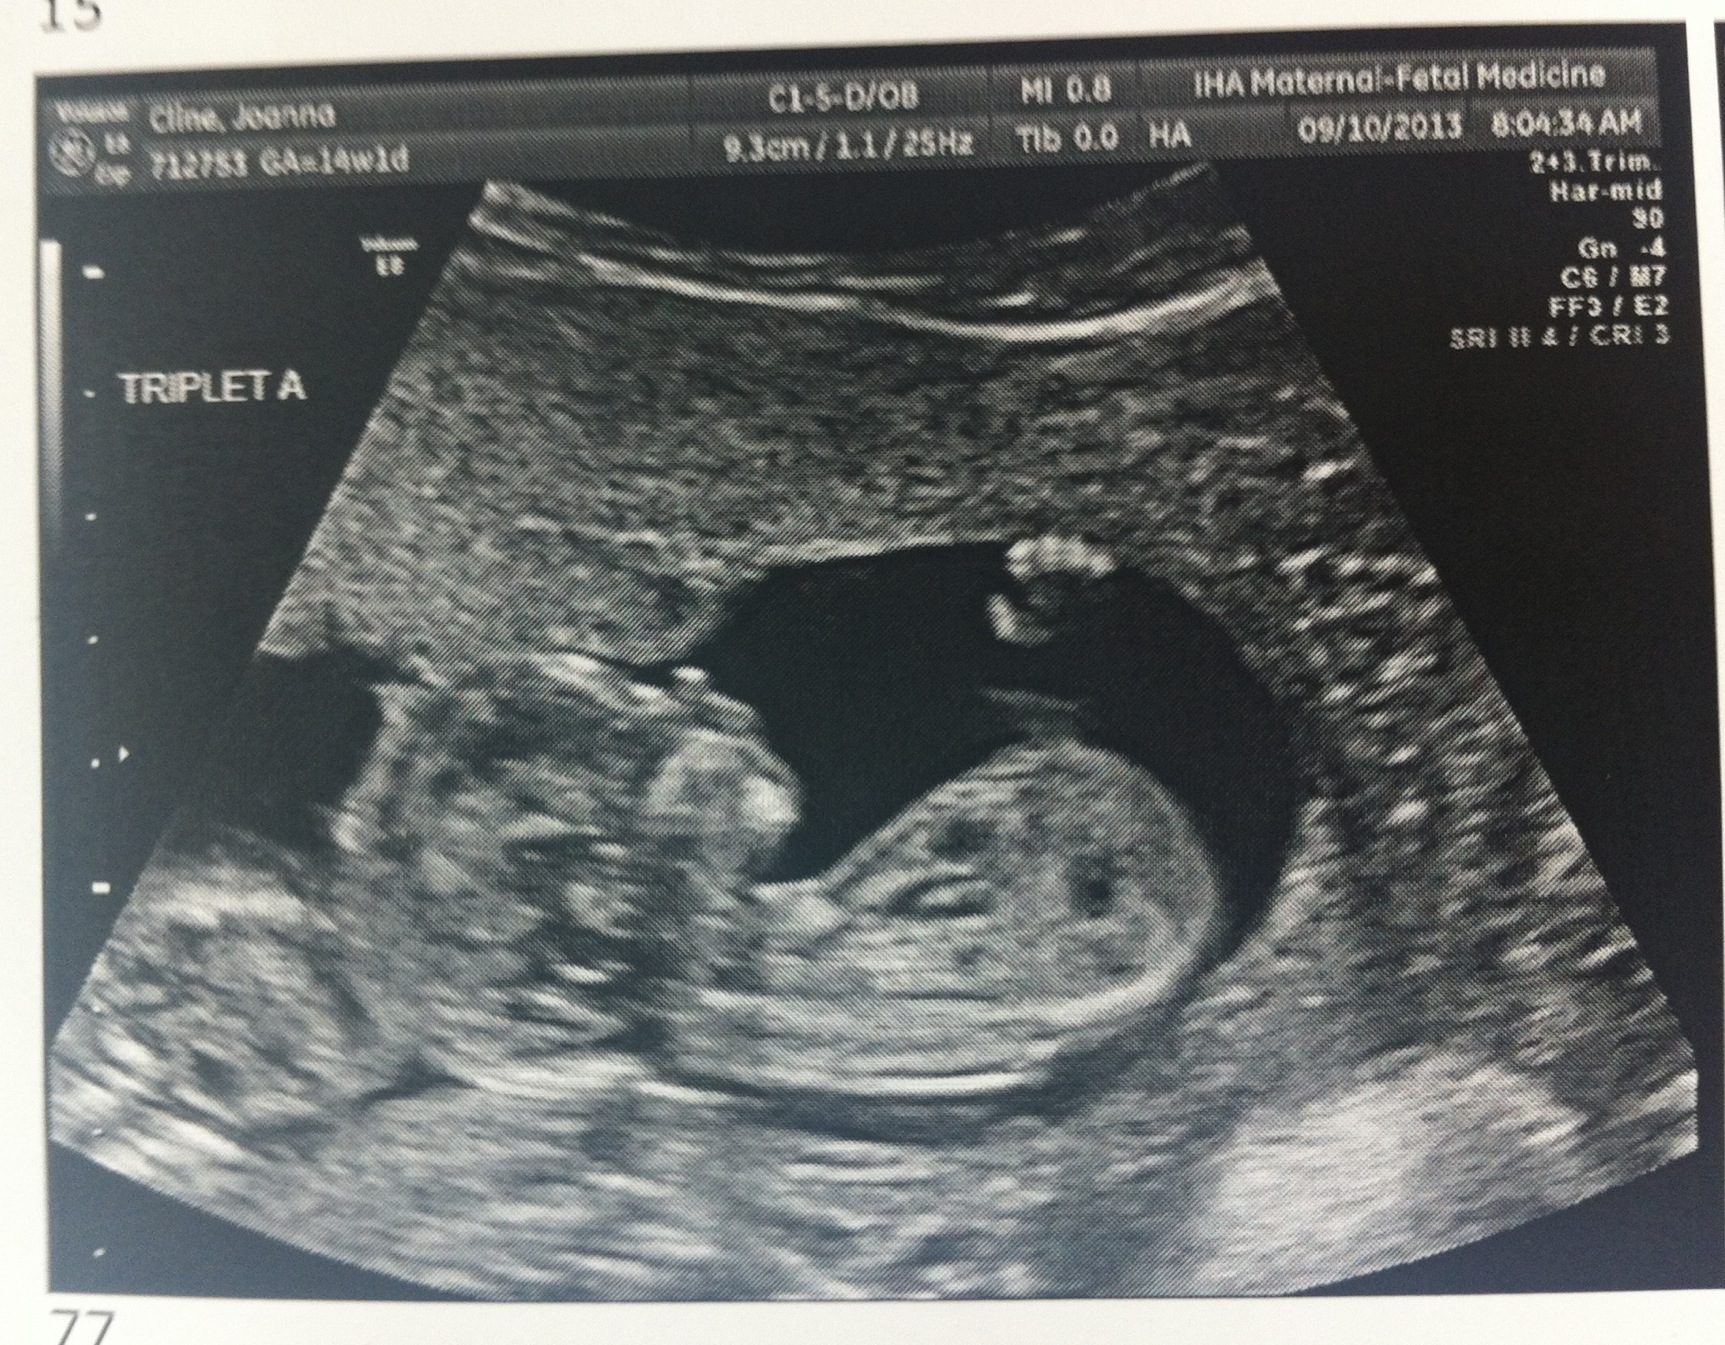

Baby A – is a BOY!

A is 170 grams, B is 175 grams and C is 178 grams so they’re all measuring well. Grow, grow, grow!